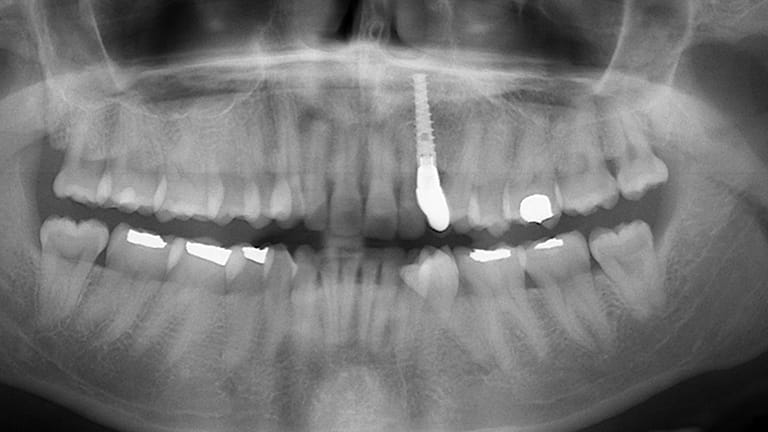

Dental implants are a titanium "root" which can be placed into the jawbone. Once integrated with your bone, the implant can be used to support a crown, a bridge, or secure a complete denture. Dental implants may be used to eliminate partial plates and dentures. The success rates for dental implants are extremely high which is due in part to the fact that root-form implants are made of a biocompatible material, titanium.

Below is a few examples of what DENTAL IMPLANTS can do for you and your smile!